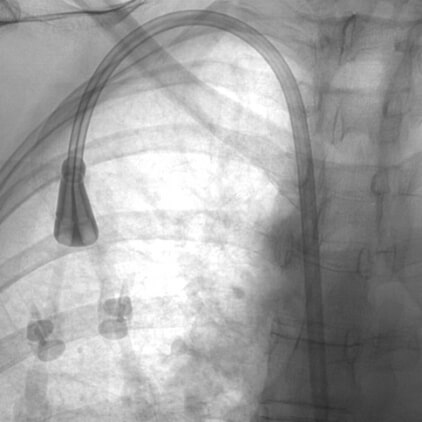

Dialysis Catheter Placement

Patients initially undergoing hemodialysis will often receive this treatment through a catheter placed into a vein in the body. These catheters can also be used as a bridge if an AV graft or fistula needs to be revised. IR is often called upon to provide this service on an acute basis and then continues their involvement to insure the proper function of these devices.